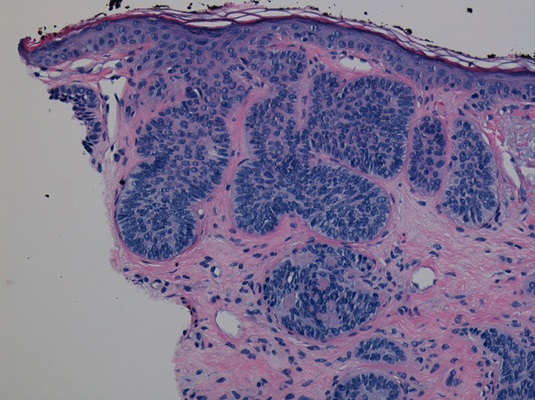

If cancer is suspected your doctor may perform a biopsy so a trained pathologist can examine the tissue and definitively determine whether or not cancer is present.

Mercy's dermatologists are seasoned experts, trained to diagnose all types of skin cancer. They work alongside experienced colleagues who can address every angle of treatment for patients in need of the highest level of care. Mercy's robust program includes medical oncologistsand surgical oncologistsoffering the most innovative therapies, dedicated pathologists with advanced training in complex cellular interpretation, and gifted plastic surgeons who use reconstructive techniques to restore confidence and reduce scarring.